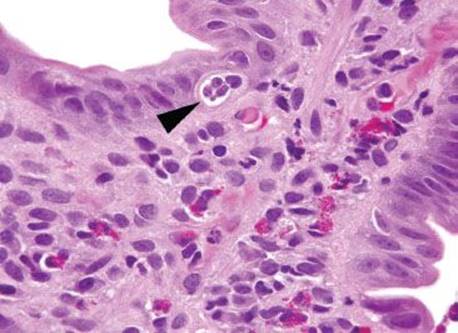

Figure 3.315 Sneaky adenocarcinoma involving the duodenal mucosa. Under oil immersion, note the nuclear irregularities, abundant pink cytoplasm, and cytoplasmic mucin droplet (arrowhead) characteristic of pancreatobiliary adenocarcinoma. Unfortunately, sometimes 38 levels are required for the ultimate diagnosis and sometimes only a few malignant cells are present! When the clinical scenario and the histology are not aligned, deeper sections (and deeper sections and deeper sections and deeper sections) are often required.